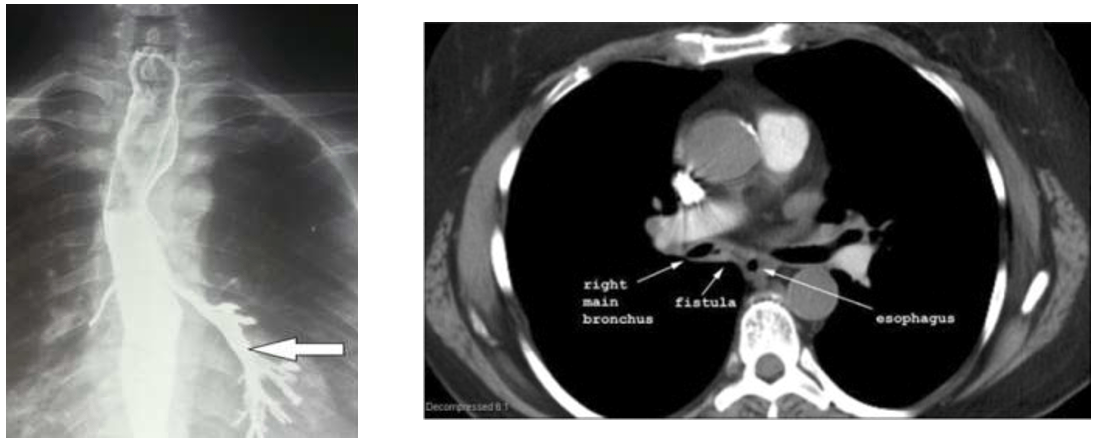

1. 기관식도루(tracheoesophageal fistula, TEF)

1) 개요

(1) 병태생리

① 기도와 식도가 비정상적으로 연결됨

② 음식물 섭취 시 식도에서 기도로 음식물이 흘러들어감 → 기도 폐쇄, 폐렴 등 발생

(2) 원인

선천성: 주로 식도폐쇄(esophageal atresia)도 동반

② 악성 질환: 식도암, 폐암

③ 기타: 장기간 기도 삽관, 기관절개술(tracheostomy), 수술, 방사선

2) 임상양상

(1) 주호소: 호흡곤란, 기침

식후 악화

(2) 기타 증상 및 징후: 반복적 폐렴, 삼킴곤란/삼킴통증

3) 검사소견

(1) 바륨식도조영술: 식도에서 trachea → bronchial tree로 조영제가 이동하는 것을 관찰

(2) CT: Trachea와 esophagus 사이의 fistula를 관찰

4) 진단: 기관지내시경 (작을 경우 관찰이 어려울 수 있으므로 methylene blue 복용 후 기도로 색소가 나오는 것을 관찰)

5) 치료

(1) 양성 질환: 수술적 교정 (더 온전하고 영구적으로 교정됨)

(2) 악성 질환: 기관지내시경 시술적 교정 (악성일 경우 수술이 큰 의미가 없는 경우가 많음)